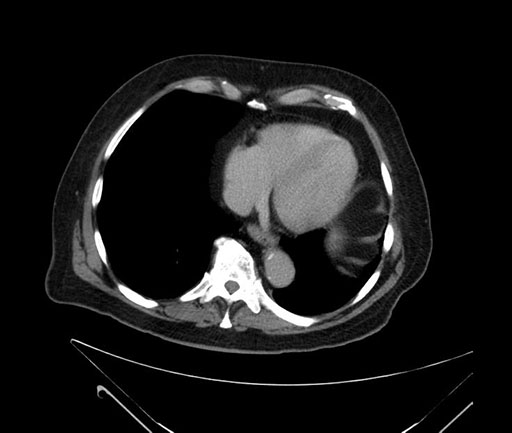

Coronal - stented